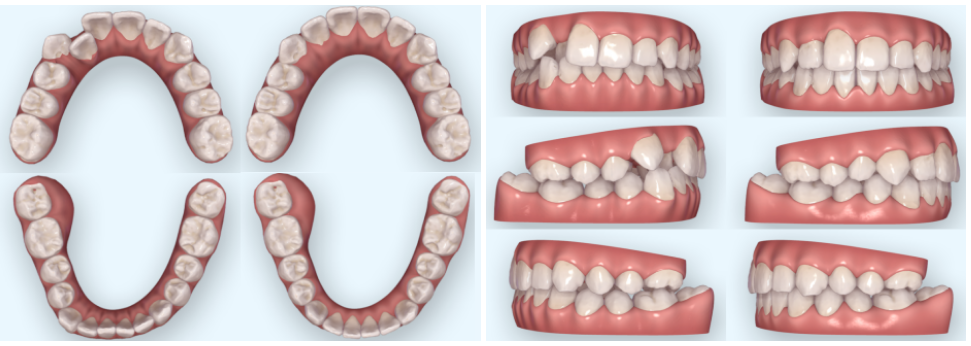

그리고 요즘에는 의료 기술력이 좋아져

미리 예측 시뮬레이션을 돌려,

지금 가지고 있는 치열에 대한 부분에서

오른쪽과 같이 개선이 될 수 있음을

눈으로 확인해 볼 수 있습니다.